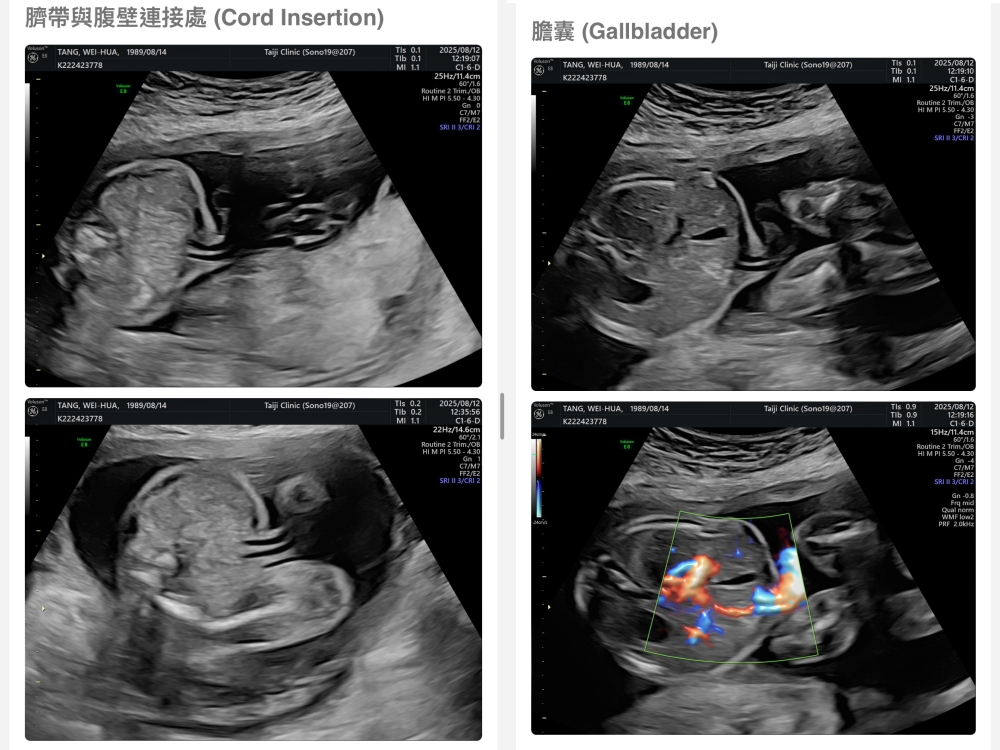

▲離開診所後會收到MAIL,我們14:05離開,大約是16:45收到mail,裡面會有滿滿的超音波照片,紀錄的很詳細!也會提供紙本的報告,可以給日後產檢的醫師做參考👌